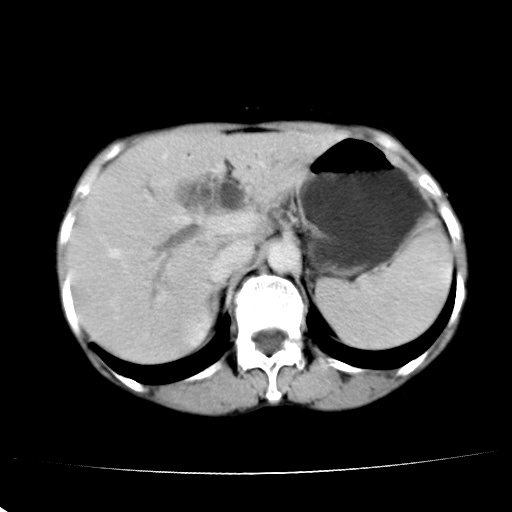

以下是引用jiangjing在2008-6-3 13:36:00的发言:[br]支持 胰头癌------肝内外胆管扩张,胰管扩张,胰头增大,增强见结节状轻度强化影,双管征明显

以下是引用卜一在2008-6-3 14:40:00的发言:[br]支持:胰头癌!(肝内外胆管扩张,胆囊高度扩张,胰管扩张,胰头增大,增强见结节状强化,明显低于胰腺强化密度,并明显见双管征)